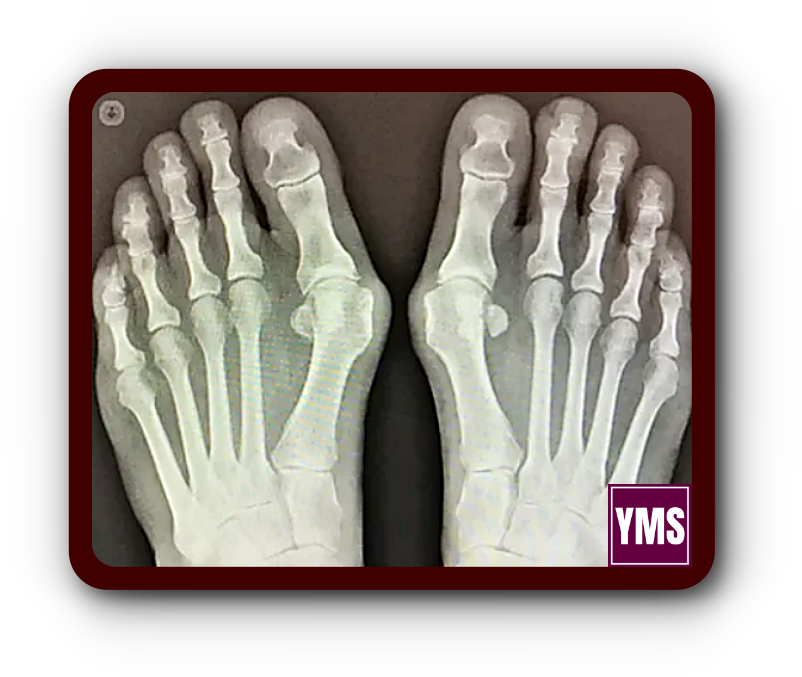

무지외반증은 엄지발가락이 바깥쪽으로 크게 휘어져 발생하는 발의 변형을 말합니다. 많은 사람들이 이 변형을 보고 무지외반증 통증이 심할 것으로 예상하지만, 실제로는 수술 후 대다수 환자가 "생각했던 것보다 통증이 적다"고 이야기합니다.

국내 한 정형외과 원장에 따르면, 무지외반증을 교정하는 수술법은 100가지가 넘습니다. 의사마다 선호하는 수술 방법이 다르고, 환자의 발 상태에 따라 최적의 수술 방법도 달라집니다.

무지외반증 수술에는 다양한 방법이 있습니다. 경도의 경우 비교적 간단한 수술을 진행하지만, 중증일 경우 더 복잡한 수술이 필요합니다.